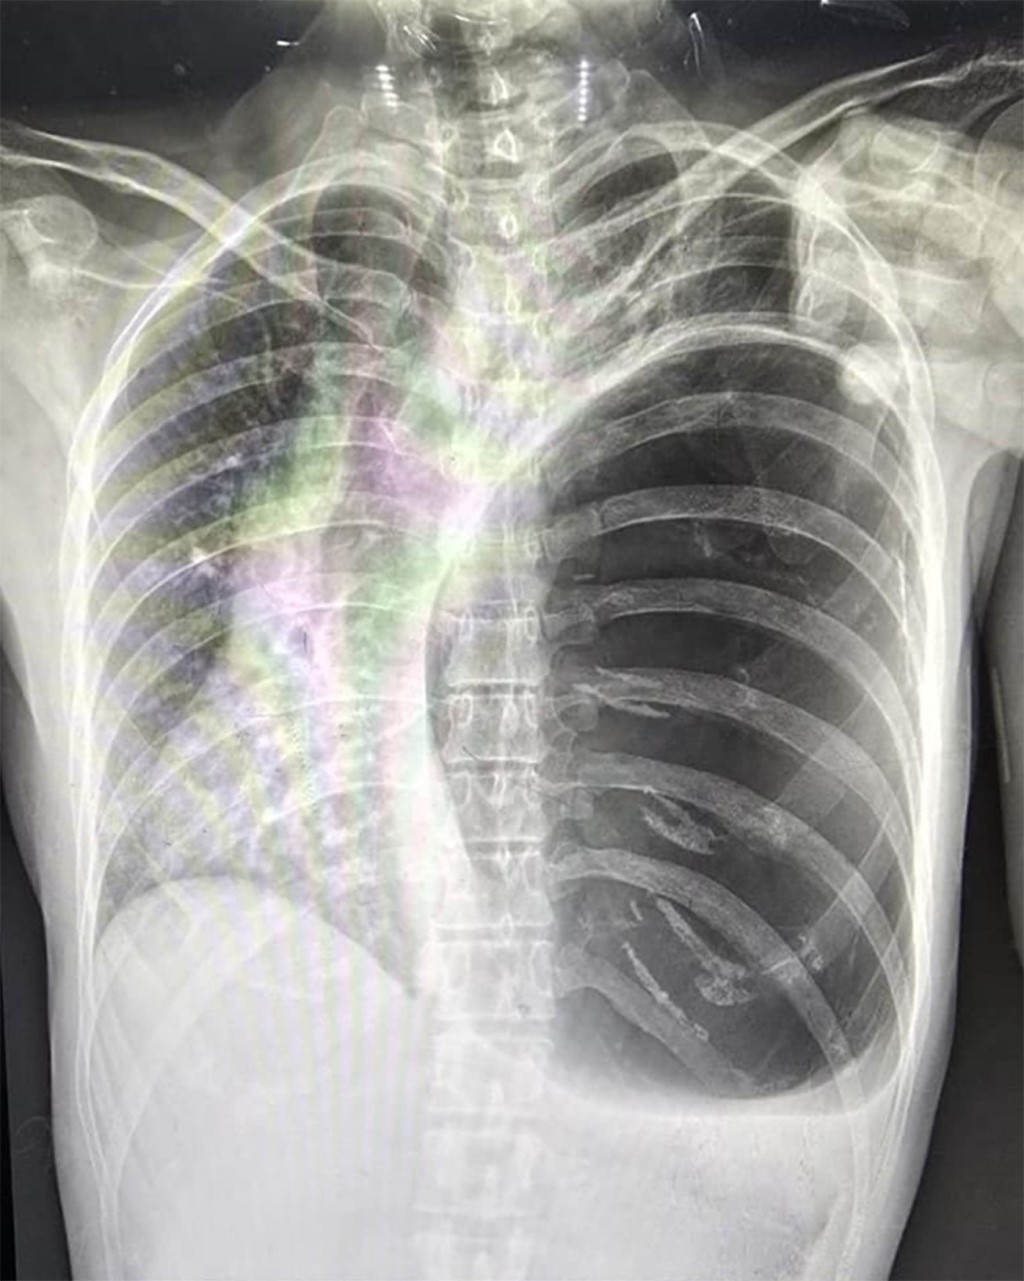

Las causas más comunes de enfisema bulloso incluyen el tabaquismo, la exposición a biomasa y la deficiencia de α-1 antitripsina. Los síntomas incluyen disnea progresiva, tos productiva, disminución de la tolerancia al ejercicio y sibilancias. Las opciones de tratamiento quirúrgico incluyen toracotomía o videotoracoscopia. Al elegir el abordaje ideal para cada paciente, se deben considerar la extensión y la ubicación de las bullas, las comorbilidades y el riesgo de recurrencia, entre otros factores. Presentamos dos casos quirúrgicos: una mujer de 45 años con antecedentes de exposición a biomasa y una bulla gigante que le causó dificultad respiratoria aguda, tratada con éxito mediante toracotomía; y un hombre de 25 años que desarrolló un neumotórax espontáneo con quistes subpleurales asociados con gran altitud, tratado mediante bullectomía videotoracoscópica.

Figura 4